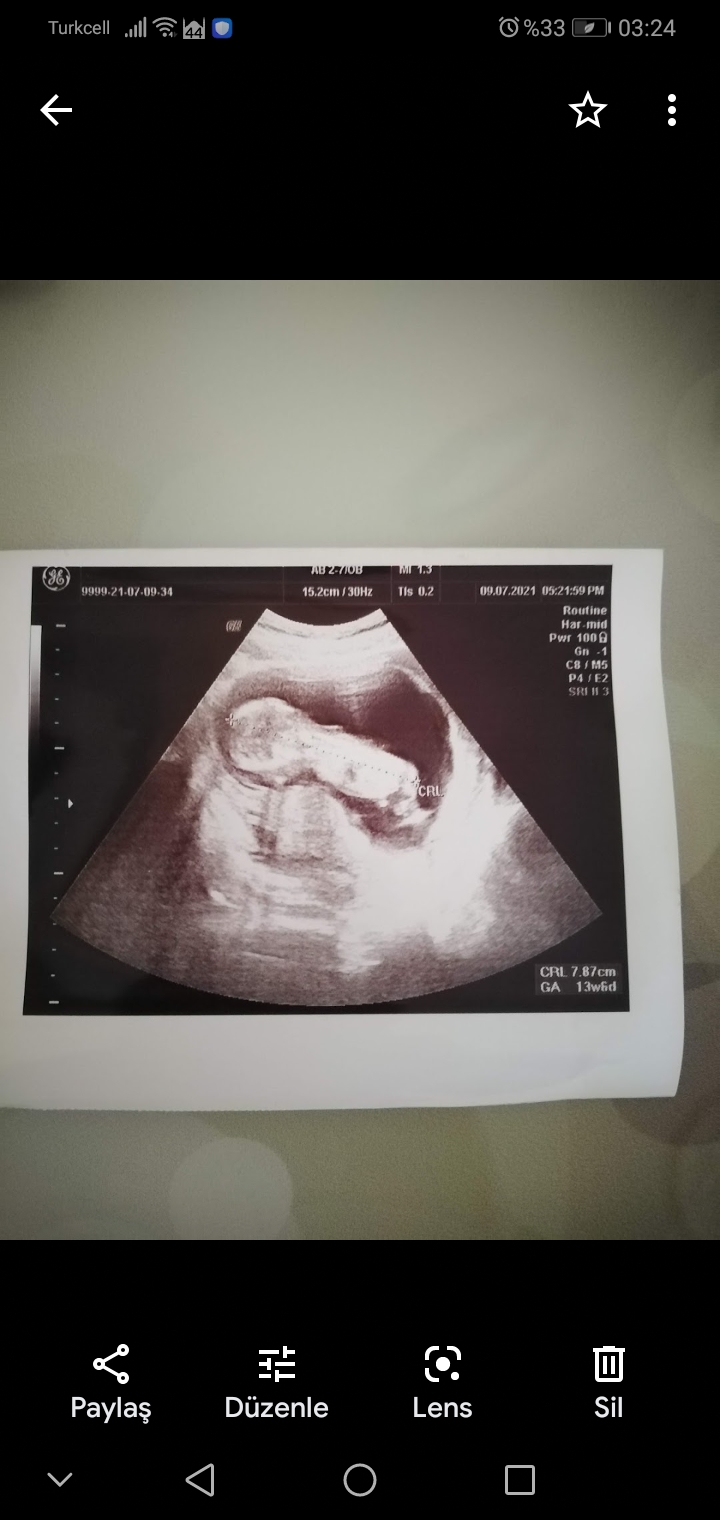

Cinsiyet tahmini bilen varmı 13 haftalık

Screenshot_20210730-032454.jpg

benimkinin cinsiyeti nedir sizce 🙂